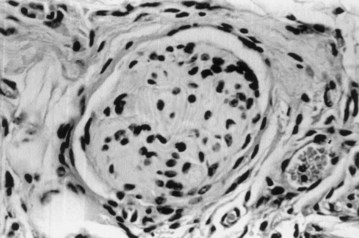

Cystectomy-only and nonseeded controls maintained average capacities of 22% and 46% of preoperative values, respectively. An average bladder capacity of 95% of the original precystectomy volume was achieved in the cell-seeded tissue engineered bladder replacements. These findings were confirmed radiographically (Fig. 19–10). The subtotal cystectomy reservoirs that were not reconstructed and the polymer-only reconstructed bladders showed a marked decrease in bladder compliance (10% and 42% total compliance). The compliance of the cell-seeded tissue-engineered bladders showed almost no difference from preoperative values that were measured when the native bladder was present (106%). Histologically, the nonseeded scaffold bladders presented a pattern of normal urothelial cells with a thickened fibrotic submucosa and a thin layer of muscle fibers. The retrieved tissue-engineered bladders showed a normal cellular organization, consisting of a trilayer of urothelium, submucosa, and muscle (Fig. 19–11). Immunocytochemical analyses confirmed the muscle and urothelial phenotype. S-100 staining indicated the presence of neural structures (Oberpenning et al, 1999). These studies, performed with polyglycolic acid–based scaffolds, have been repeated by other investigators, showing similar results in large numbers of animals long-term (Jayo et al, 2008a, 2008b). The strategy of using biodegradable scaffolds with cells can be pursued without concerns for local or systemic toxicity (Kwon et al, 2008). However, not all scaffolds perform well if a large portion of the bladder needs replacement. In a study using SIS for subtotal bladder replacement in dogs, both the unseeded and cell-seeded experimental groups showed graft shrinkage and poor results (Zhang et al, 2006b). The type of scaffold used is critical for the success of these technologies. The use of bioreactors, wherein mechanical stimulation is started at the time of organ production, has also been proposed as an important parameter for success (Farhat et al, 2008).

Figure 19–11 Hematoxylin and eosin staining shows histologic results 6 months after surgery (original magnification, ×250). A, Normal canine bladder. B, The bladder dome of the bladder reconstructed with cell-free polymer consists of normal urothelium over a thickened layer of collagen and fibrotic tissue; only scarce muscle fibers are apparent. C, The tissue-engineered neo-organ has a histomorphologically normal appearance. A trilayered architecture consisting of urothelium, submucosa, and smooth muscle is evident.